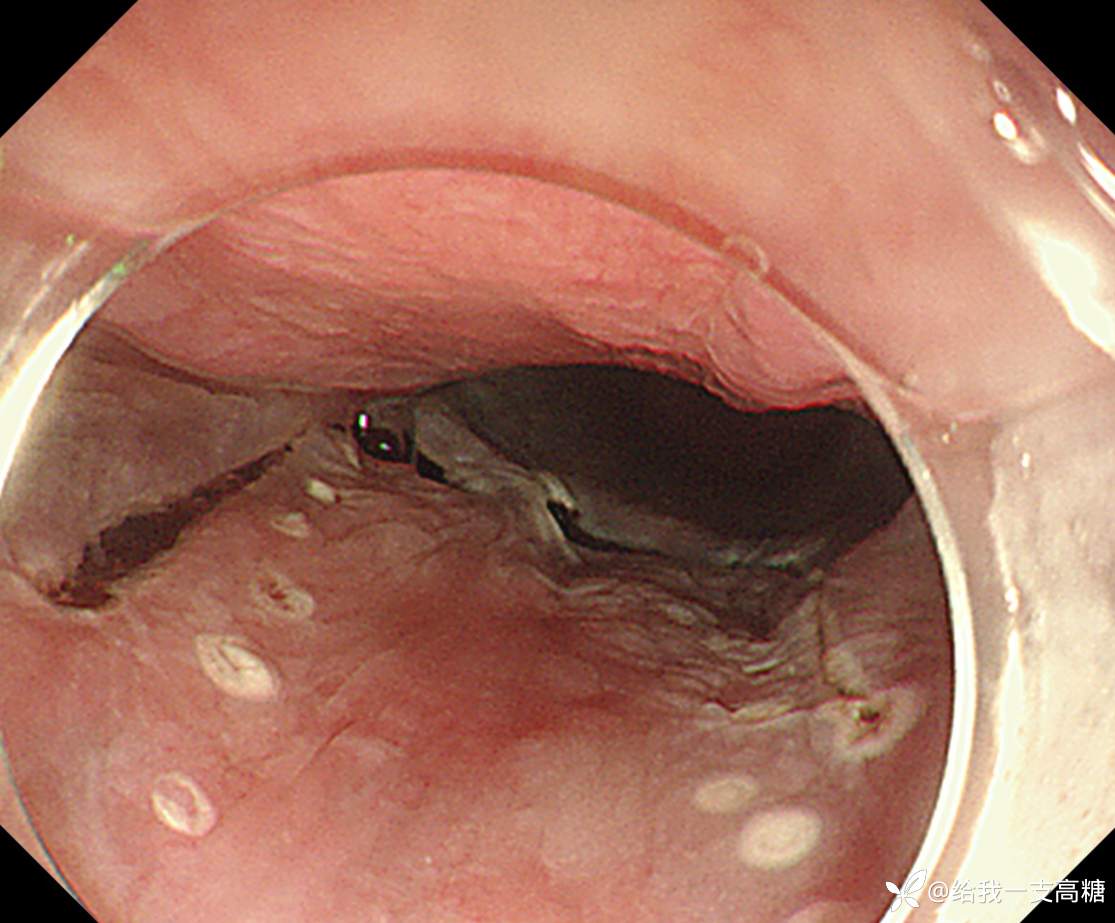

完整剥离、固定

术后病理局部鳞状上皮呈高级别异型增生